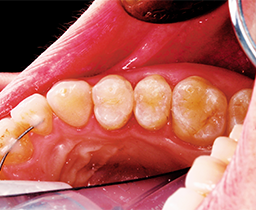

A 32 year-old female patient presented to the practice for her routine examination. The radiographs revealed primary lesions located interproximally (Fig. 1a). The patient was diagnosed with primary caries on tooth #5 DO (Fig. 1b). The clinical objective was to successfully remove caries and restore the tooth while delivering an optimal patient experience.

The final result was an esthetically-pleasing restored tooth (Figs. 6-7)

Fig. 6 Fig. 7